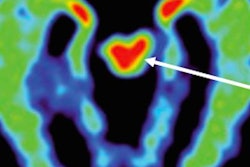

FDDNP-PET signals in the subcortical (caudate, putamen, thalamus, subthalamus, midbrain, cerebellar white matter) and cortical regions of the brain (amygdala, frontal, parietal, posterior cingulate, medial and lateral temporal) were compared with results of five male controls of comparable age, education, and body mass index.

| Left images show normal brain scans; middle and right images show scans of football players. Green and red colors demonstrate a higher level of tau protein. Scans of the players in the study reflect differing levels of tau protein and follow a pattern of progression similar to the tau deposits that have been observed at autopsy in CTE cases. Image courtesy of David Geffen School of Medicine at UCLA. |

The FDDNP-PET images showed that the former NFL players had significantly greater FDDNP signals than the controls in the caudate, putamen, thalamus, subthalamus, midbrain, and cerebellar white-matter regions. The athletes and the healthy control group did not differ significantly in FDDNP binding in cortical regions except for the amygdala.

The amygdala and subcortical regions of the brain control learning, memory, behavior, emotions, and other mental and physical functions.

The results "suggest a link between the players' history of head injury and FDDNP binding," Small and colleagues concluded. "Moreover, these binding patterns (high subcortical and low cortical binding except for the amygdala) are consistent with tau deposition patterns observed in autopsy studies of CTE and differ from those observed in patients with cognitive and mood symptoms without prior head trauma, who mainly present with increased cortical FDDNP binding."